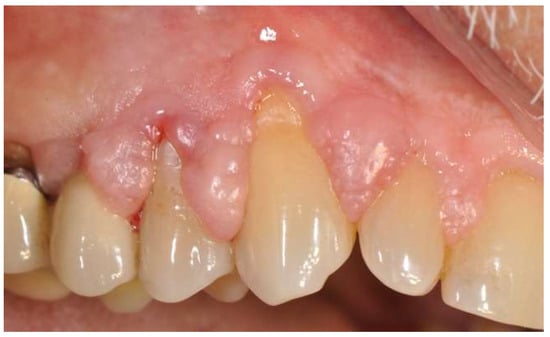

2. Case Presentation

2.1. Surgical Procedure